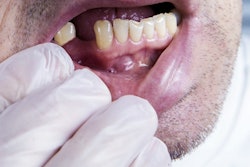

A 26-year-old man presented with facial swelling on his left side and trismus. Images courtesy of Cordero et al. Licensed by CC BY 4.0.

A 26-year-old man presented with facial swelling on his left side and trismus. Images courtesy of Cordero et al. Licensed by CC BY 4.0.Lab results showed the man had an elevated white blood cell count, and a CT scan depicted a 2.9 × 3.6 × 2.2-cm collection of fluid in the lateral pterygoid, suggesting an infratemporal fossa abscess. Due to abscess' proximity to the buccal mucosa and to provide immediate pain relief, the abscess was drained. A fluid sample was sent to the lab for testing, Cordero et al wrote.